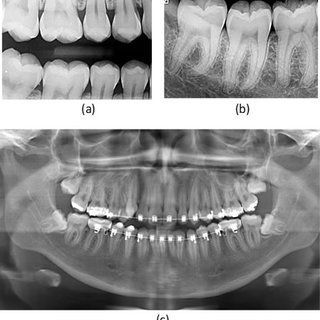

Bitewing radiographs provide vital information to aid in the diagnosis of the most common dental diseases; specifically tooth decay and periodontal bone loss or gum disease. Additional important findings may be detected on bitewings, including the condition of fillings and the presence of calculus or tartar.